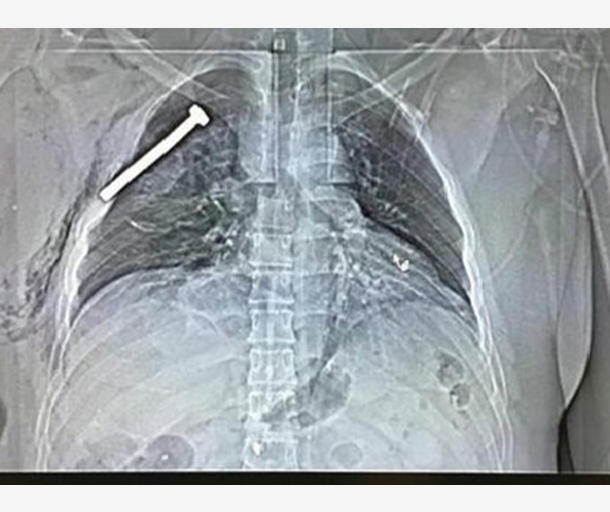

صور بأشعة X لمسامير اخترقت ضحايا تفجيرات بروكسل

23 مارس 2016 , 11:32ص